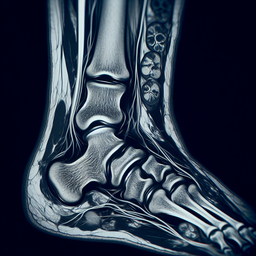

**Переваги МРТ:**

- Висока точність у виявленні пошкоджень зв’язок, сухожиль, м’язів та хрящів.

- Відсутність опромінення, що робить процедуру безпечною.

- Дозволяє виявити запальні процеси, набряки та зміни в структурі тканин.

**Показання для проведення:**

- Біль у гомілково-ступневому суглобі.

- Підозра на розрив зв’язок або сухожиль.

- Вивихи та переломи.

- Артрити та артрози.

- Остеомієліт або інші інфекційні процеси.